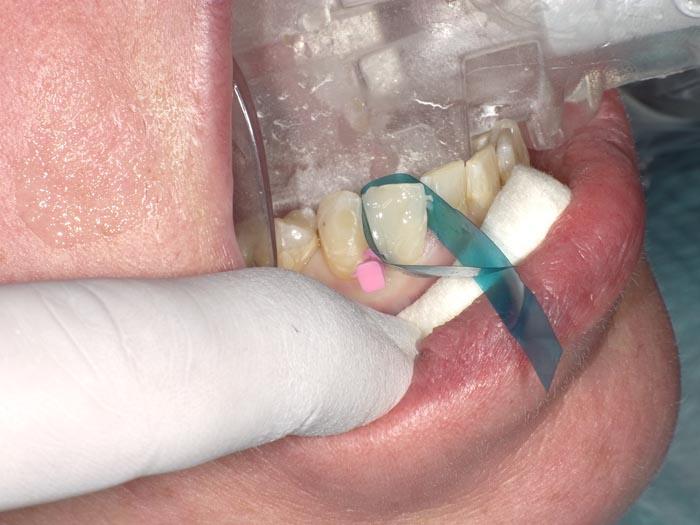

Case 1

A 37-year-old patient presented for treatment after years of neglect. After administering anesthetic and placing an Isolite isolation device, we prepared teeth #10–12 and restored them

with Activa Bioactive-Restorative composite.